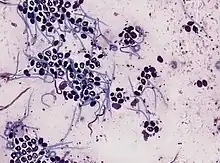

- A taxonomic genus within the family Onchocercidae – parasitic roundworms that cause river blindness.